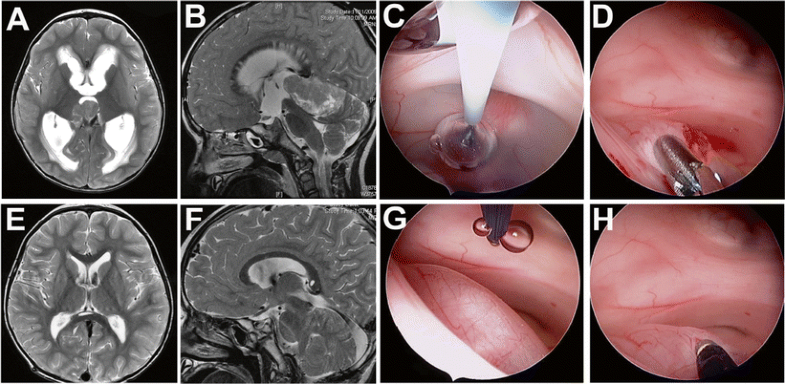

Three-year-old presenting with progressive imbalance, nausea, and vomiting. Initial MRI demonstrated a large pineal region tumor extending into the third ventricle and significant obstructive hydrocephalus with periventricular edema (a, b). An endoscopic third ventriculostomy (c) followed by a tumor biopsy (d) was performed. The pathological diagnosis was pinealoblastoma, and a supracerebellar infratentorial approach was chosen for tumor resection. Follow-up MRI demonstrated resolution of the hydrocephalus (e) and a gross total tumor resection was achieved (f). To reach the tumor, a burr hole was placed slightly more frontal than the classic Kocher’s point. This, together with an enlarged foramen of Monro, allowed access to the posterior part of the third ventricle. To improve visualization and control of endoscopic instruments in the tumor, the endoscope was rotated 180°, placing the working channel close the lesion. g Prior to rotation, note instrument at 12 o’clock away from lesion. h Instrument at 6 o’clock with good access to the tumor